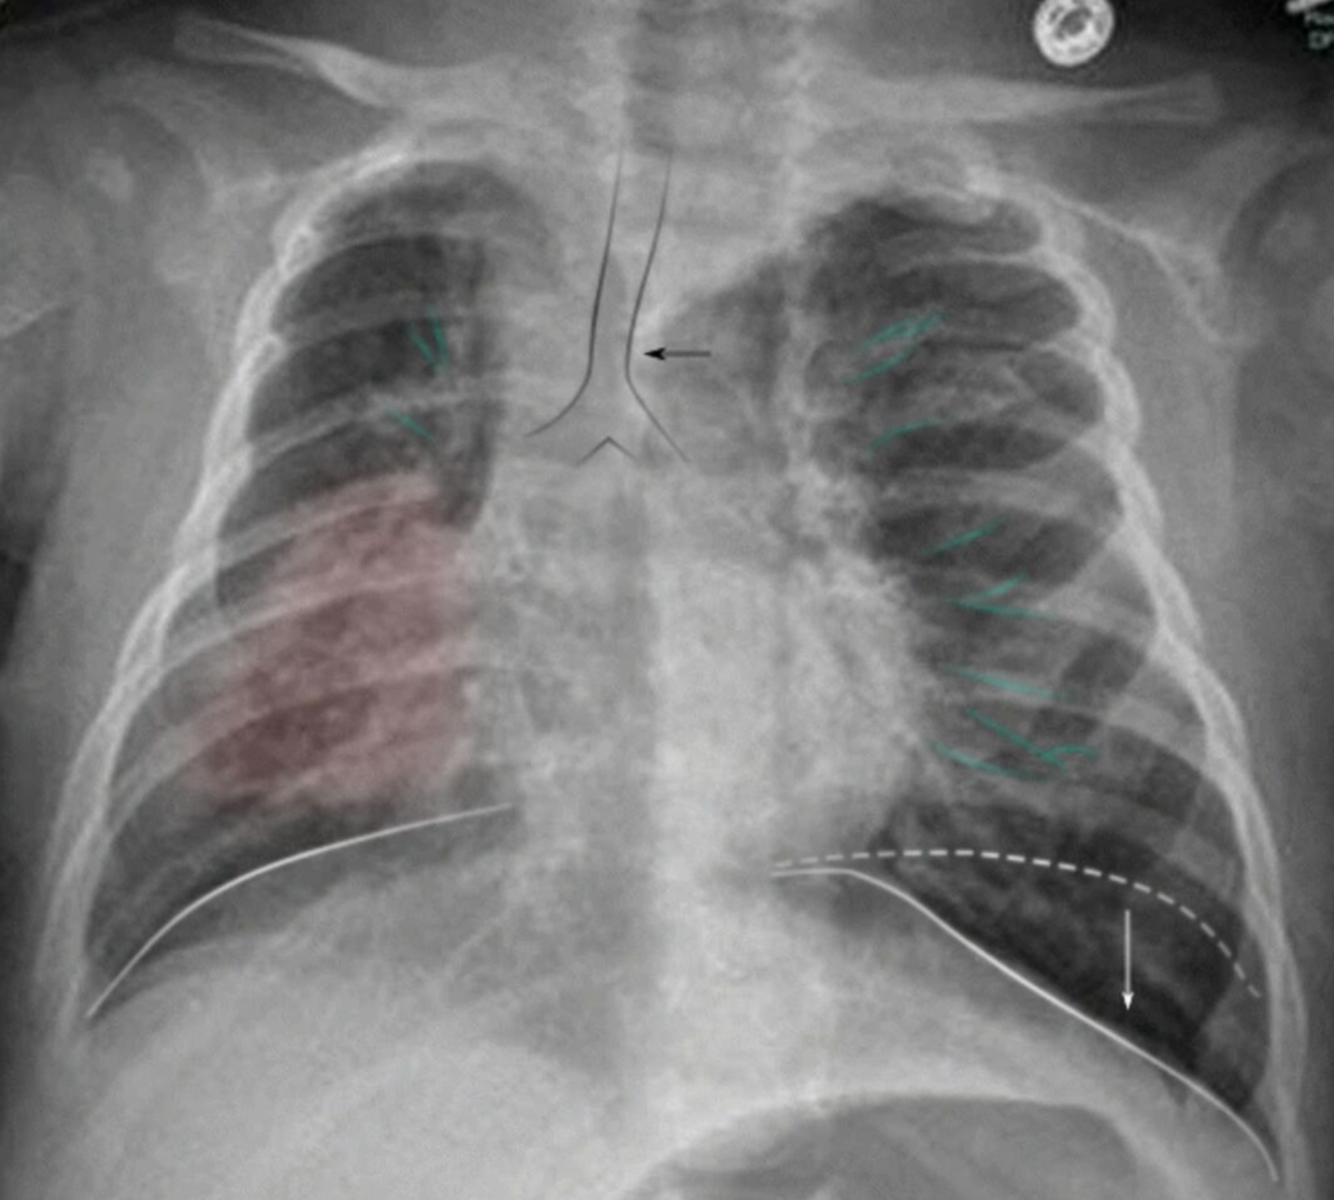

Bilateral hyperinflation and right lung consolidation

X-ray chest (AP view) of a child with viral bronchiolitis and focal pneumonia

Bilateral perihilar peribronchial thickening (examples of bronchi indicated by green lines) is accompanied by hyperinflation with diaphragmatic depression (indicated by white lines and arrow). In the right lung, a superimposed area of consolidation from pneumonia (red overlay) is associated with atelectasis and ipsilateral mediastinal shift (indicated by black arrow).

Black outline: trachea; white dashed line: physiological position of left hemidiaphragm